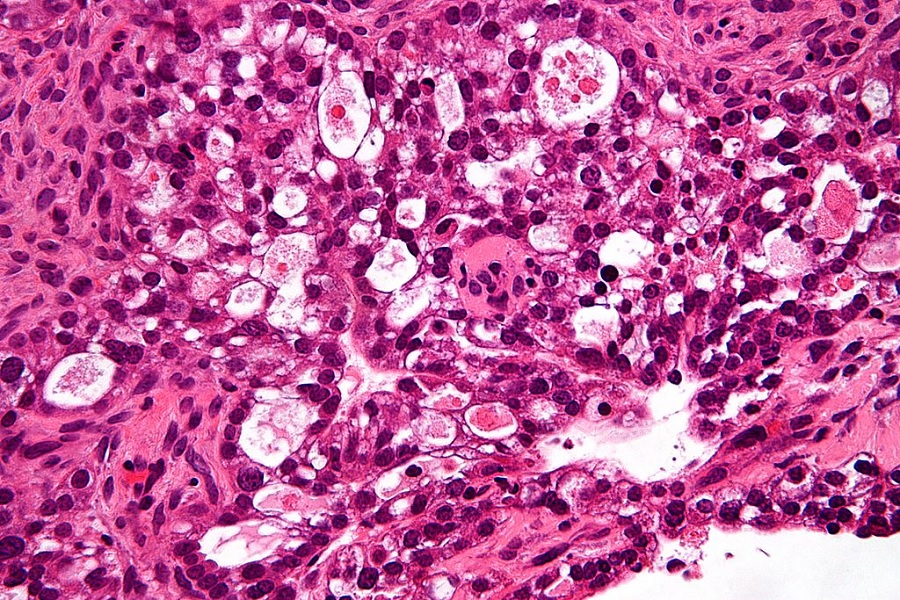

The paper, published in Molecular Cancer Research, reported that high-grade serous carcinoma (HGSC) is the most commonly diagnosed and fatal type of epithelial ovarian cancer. While treatments currently exist for this type of cancer, scientists observed that a high number of HGSC-diagnosed patients tend to be resistant or to relapse from chemotherapies.

Scientists learned that HGSC cells favor using glucose in the citric acid cycle and not for aerobic glycolysis as normal cells do. In other cases, cancer cells are known to prefer the aerobic glycolysis to convert sugar to energy, so it is the focus of other treatments.

However, the study found that a “wild-type” of IDH1 is greatly linked to the citric acid cycle and the enzyme’s protein production is increased among patients with HGSC cells. This discovery paves the way for new treatment strategies effectively targeting IDH1 with the spread of HGSC cells. The researchers observed that through pharmacological inhibition, targeting IDH1 reduced the spread of HGSC cells.